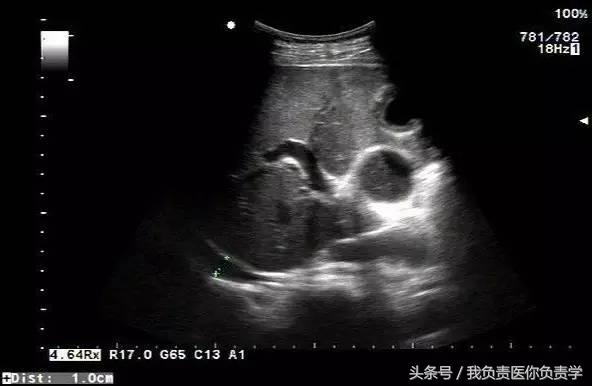

典型病例 1

患者男,64岁,因右上腹疼痛半月余就诊。查体发现右上腹部轻压痛,无发热。超声检查所见如下:

图1示胆囊增大,囊壁增厚,囊内透声差

图2示于胆囊外侧可见一局限性囊性无回声区

图3示胆囊与囊性回声区间隐约可见裂隙相通

图4和5为局部放大图像,可见胆囊与囊性回声区间可见直径约2mm的通道

超声检查考虑为胆囊炎合并胆囊穿孔,后经CT检查证实。